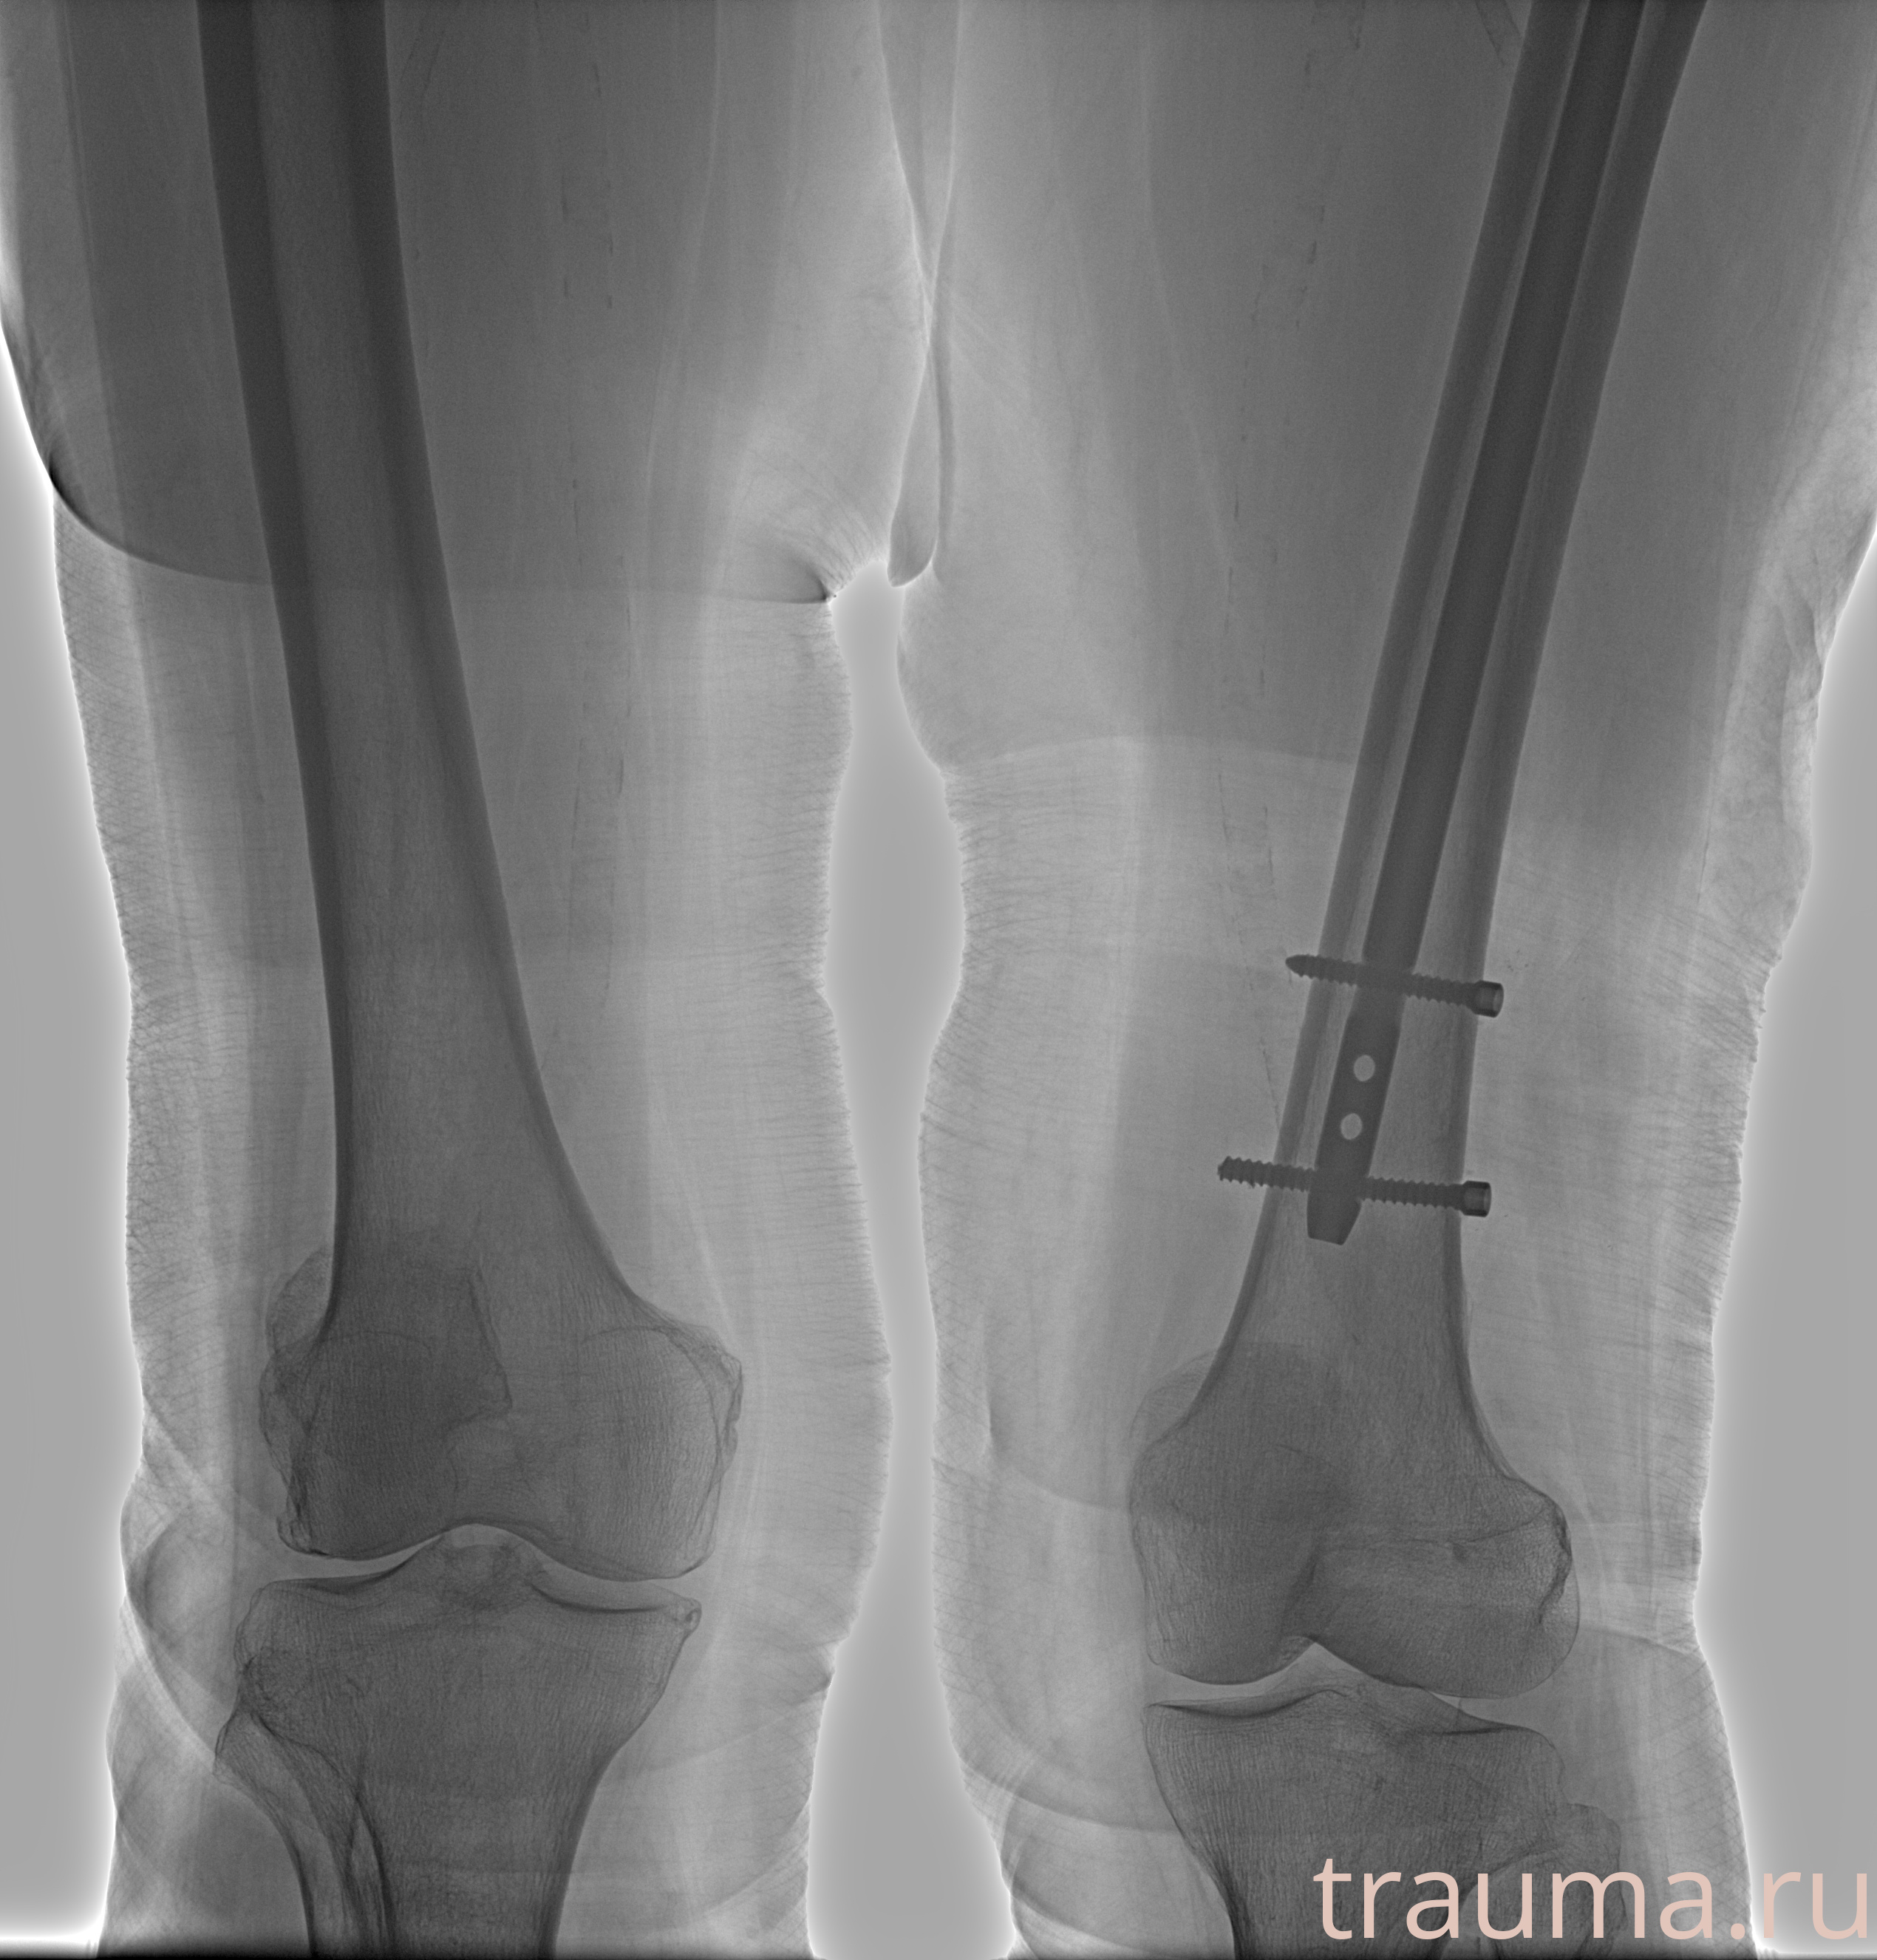

Рентгенограммы

24.01.2026

Рентген на дому: по вашему адресу приезжает врач-рентгенолог, травматолог-ортопед с мобильным рентгеновским аппаратом, проводит диагностику травмы или заболевания, делает необходимые рентгенограммы, дает рекомендации по дальнейшему лечению. Получить качественные снимки в домашних условиях возможно благодаря уникальной методике, разработанной МосРентген Центром для института  Склифосовского